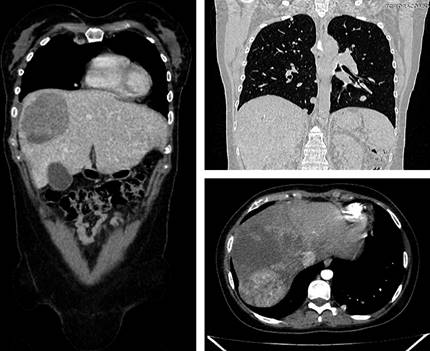

En este caso, se apreció un beneficio de esta terapia al haber una disminución significativa de la enfermedad (Figura 2), alcanzando una supervivencia libre de progresión de 18.13 meses y una supervivencia global de 22.23 meses.